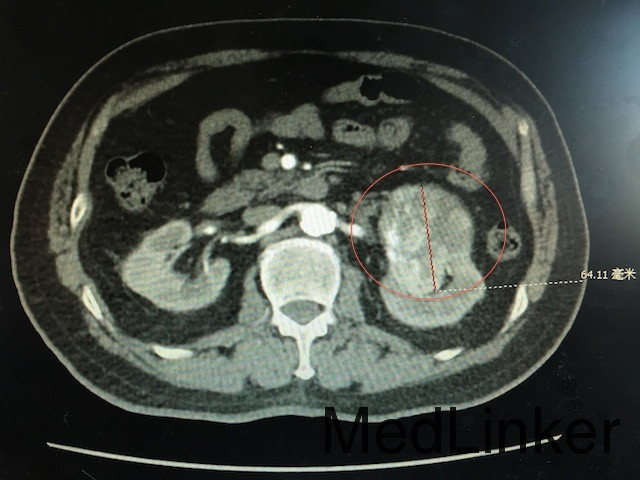

查体:左肾区叩痛可疑阳性 辅助检查:泌尿系CT平扫+强化如下图所示:左肾下极可见软组织密度团块影,突出肾轮廓并累及肾窦,大小约为6.6*6.1*5.7cm,动脉期呈不均匀强化,可见左肾动脉分支血供。

诊断:肾占位(肾恶习肿瘤可能性大) 治疗:肾癌根治术

随访:肾及肾周包膜切除,病理回报为肾透明细胞癌 讨论:肾恶性肿瘤主要与肾错构瘤鉴别,后者B超可见脂肪密度高回声,CT平扫为脂肪密度,CT增强强化比肾恶性肿瘤更明显。